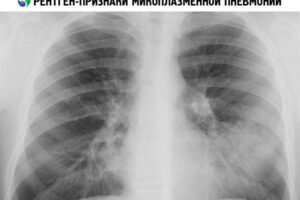

Микоплазменная пневмония — что это, симптомы, чем лечить

Mycoplasma pneumoniae — инфекционная патология легочной системы, симптомы которой мало чем отличаются от классической пневмонии. Научные исследования подтвердили, что это заболевание развивается в результате пониженного иммунитета и постоянного воздействия стрессов. Заражение болезнетворными микроорганизмами происходит воздушно-капельным путем. Разница между микоплазменной пневмонией и нормальной пневмонией заключается в способах ее диагностики и лечения, а также в шансах на …